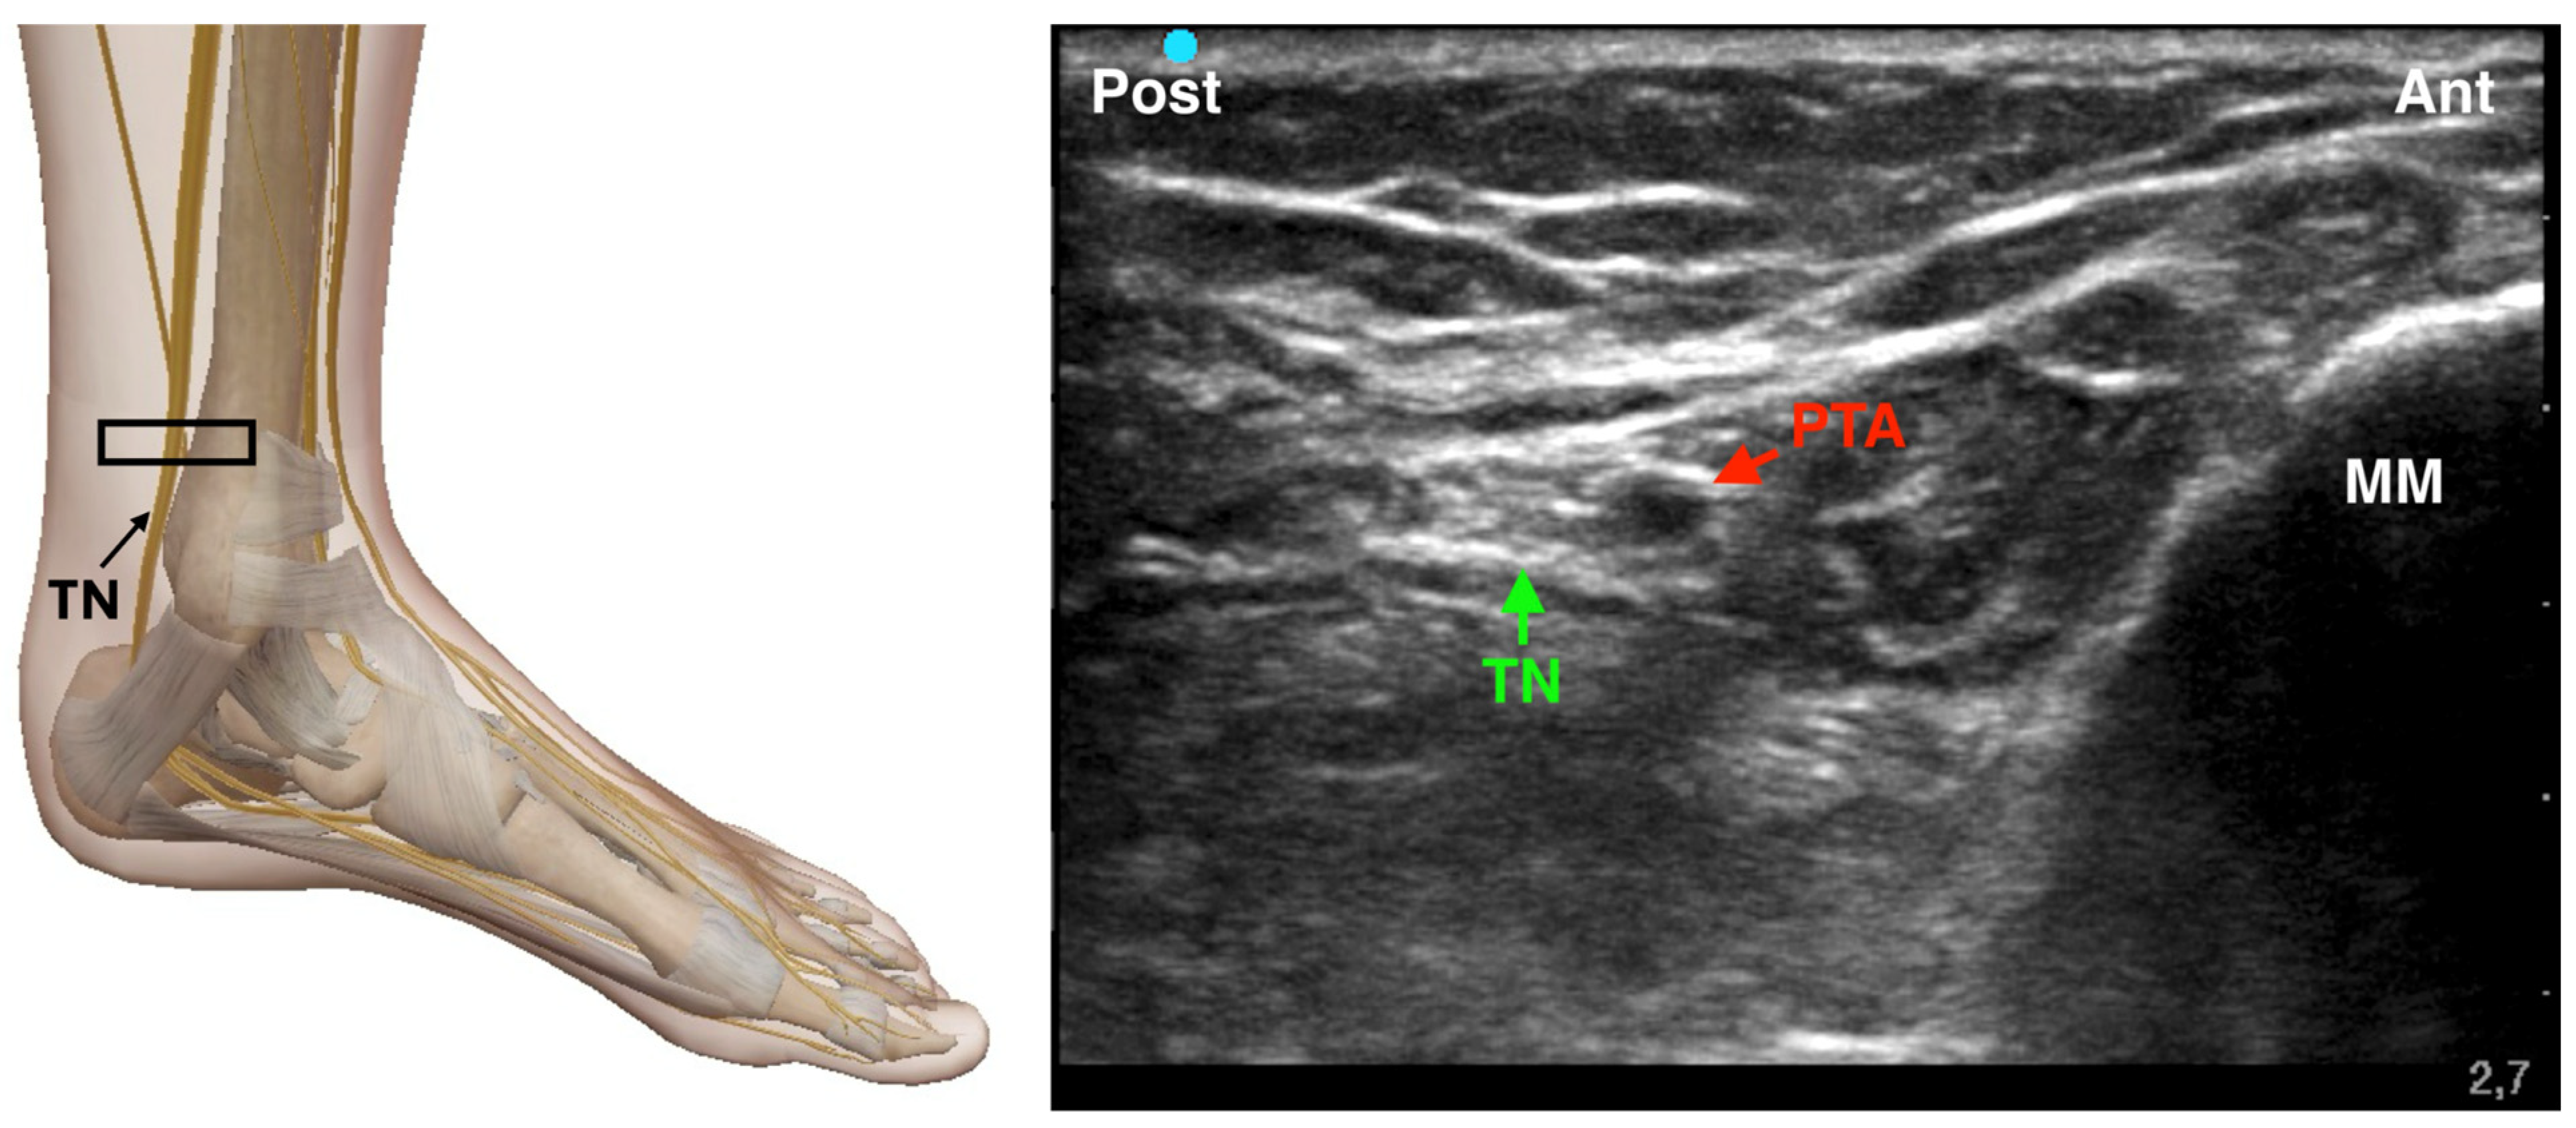

4.3.1. Tibial Nerve Block

The tibial nerve is the largest branch of the sciatic nerve and provides sensory innervation to the plantar surface of the foot, as well as motor control to its intrinsic muscles. It is located posterior to the medial malleolus, coursing alongside the posterior tibial artery and veins within the tarsal tunnel. Tibial nerve blockade can be performed using either a landmark-based or an ultrasound-guided approach. The traditional technique, described by Brown, relies on palpation of anatomical landmarks—namely, the Achilles tendon and the medial malleolus—rather than direct nerve visualization [20]. In this method, the needle is inserted medial to the Achilles tendon at the superior border of the medial malleolus and directed toward the malleolus. If paresthesia is elicited in the foot, local anesthetic is injected; if not, the needle is repositioned by advancing, altering its angle, or contacting bone and withdrawing slightly (2–3 mm) before injection. In contrast, the ultrasound-guided technique offers direct visualization of the tibial nerve and surrounding structures, enhancing both precision and safety [25]. A high-frequency linear transducer is placed in a transverse orientation posterior to the medial malleolus. The tibial nerve appears as a hyperechoic structure adjacent to the posterior tibial artery (Figure 3). Using an in-plane technique, a 22-gauge needle is advanced from posterior to anterior, and 3–5 mL of local anesthetic (e.g., 0.5% ropivacaine or 2% mepivacaine) is injected circumferentially around the nerve. Aspiration prior to injection is essential to avoid intravascular administration. Both techniques can be effective; however, Redborg et al. demonstrated that ultrasound guidance—particularly through identification of the posterior tibial artery—yields a higher success rate compared to landmark-based methods, which depend more heavily on surface anatomy and require smaller volumes of local anesthetic [6].

Figure 3. Ultrasound-guided Tibial Nerve Block. TN: Tibial Nerve; PTA: Posterior Tibial Artery; MM: Medial Malleolus; The black rectangle indicates the placement of the ultrasound probe on the anatomical area.